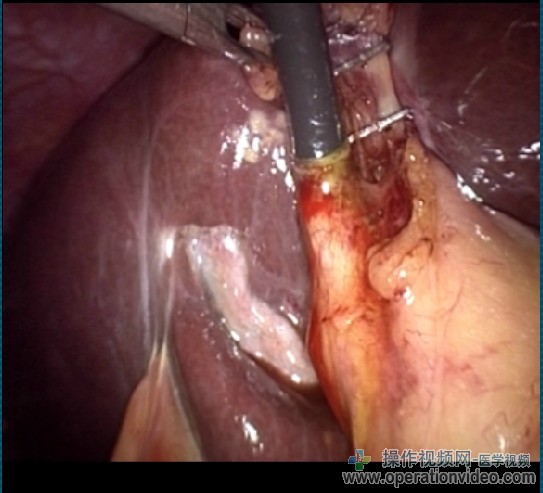

内镜引导下取石,包括以下步骤:

-胆道镜的引进和可视化的石头(S);

-引进的Dormia篮通过操作通道(或胆道镜一起)进入CBD。石头检索,由Dormia购物篮针对所述内窥镜的前端牢固地保持

胆道镜与Dormia篮子在持续的视图被撤回。